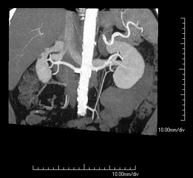

- Abdominal aorta CT angiography

A non-invasive diagnostic test that involves studying the abdominal aorta by obtaining high-definition anatomical images using CT (computed tomography) equipment and iodinated contrast. With the aid of workstations specialised for arterial studies, the image quality supports 2D and 3D reconstructions. It is indicated in patients with vascular disease (atherosclerosis), aortic aneurysms, abdominal pain of possible vascular origin, pre-surgical studies of lesions adjacent to the abdominal aorta as a vascular ‘map’, etc. Information obtained non-invasively is indispensable for patients requiring percutaneous or surgical processing. In patients who only require tracking of vascular lesions, this technique is the non-invasive technique of choice, together with MRI angiography.

- Renal artery CT angiography

A non-invasive diagnostic test that involves studying the renal arteries by obtaining high-definition anatomical images using CT (computed tomography) equipment and iodinated contrast. With the aid of workstations specialised for arterial studies, the image quality supports 2D and 3D reconstructions. This test is recommended, for example, in patients suffering from refractory hypertension that does not respond to processing, in patients with kidney damage in order to obtain a pre-surgical ‘vascular’ map, etc.